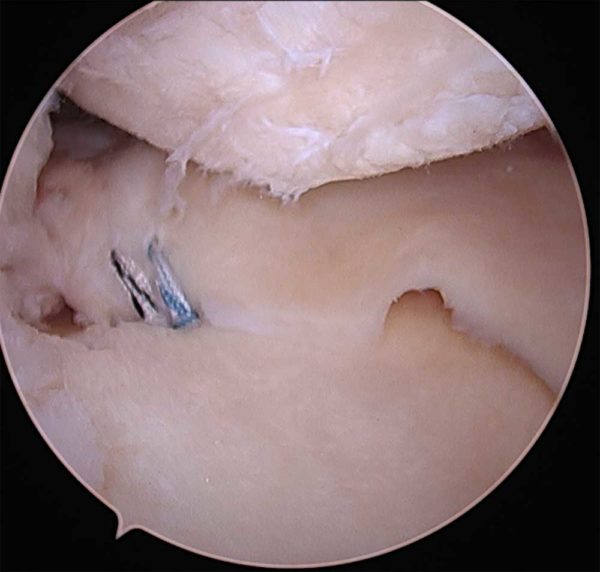

Sutures are passed through the meniscus, and then pulled down into a bone tunnel located at the same site as the root attachment before it tore.

Sutures are passed through the meniscus, and then pulled down into a bone tunnel located at the same site as the root attachment before it tore. There are three options for treating a torn meniscus, depending on the location and the extent of the tear: This allows the meniscus to heal back to the bone.

The first of these is wearing the correct footwear for the sport and surface that the activity is taking place on. These root attachments can tear with injury. Root repairs are performed arthroscopically by suturing the meniscus root to its native attachment site.

The most common method to fix meniscus root tears is through a tibial bone tunnel. Cortisone injections may temporarily decrease the pain associated with a tear but cannot heal a meniscus tear. 717.4 derangement of the lateral meniscus 717.3 derangement of the medial meniscus 836.0 lateral meniscus tear 836.1 medial meniscus tear case type / diagnosis: